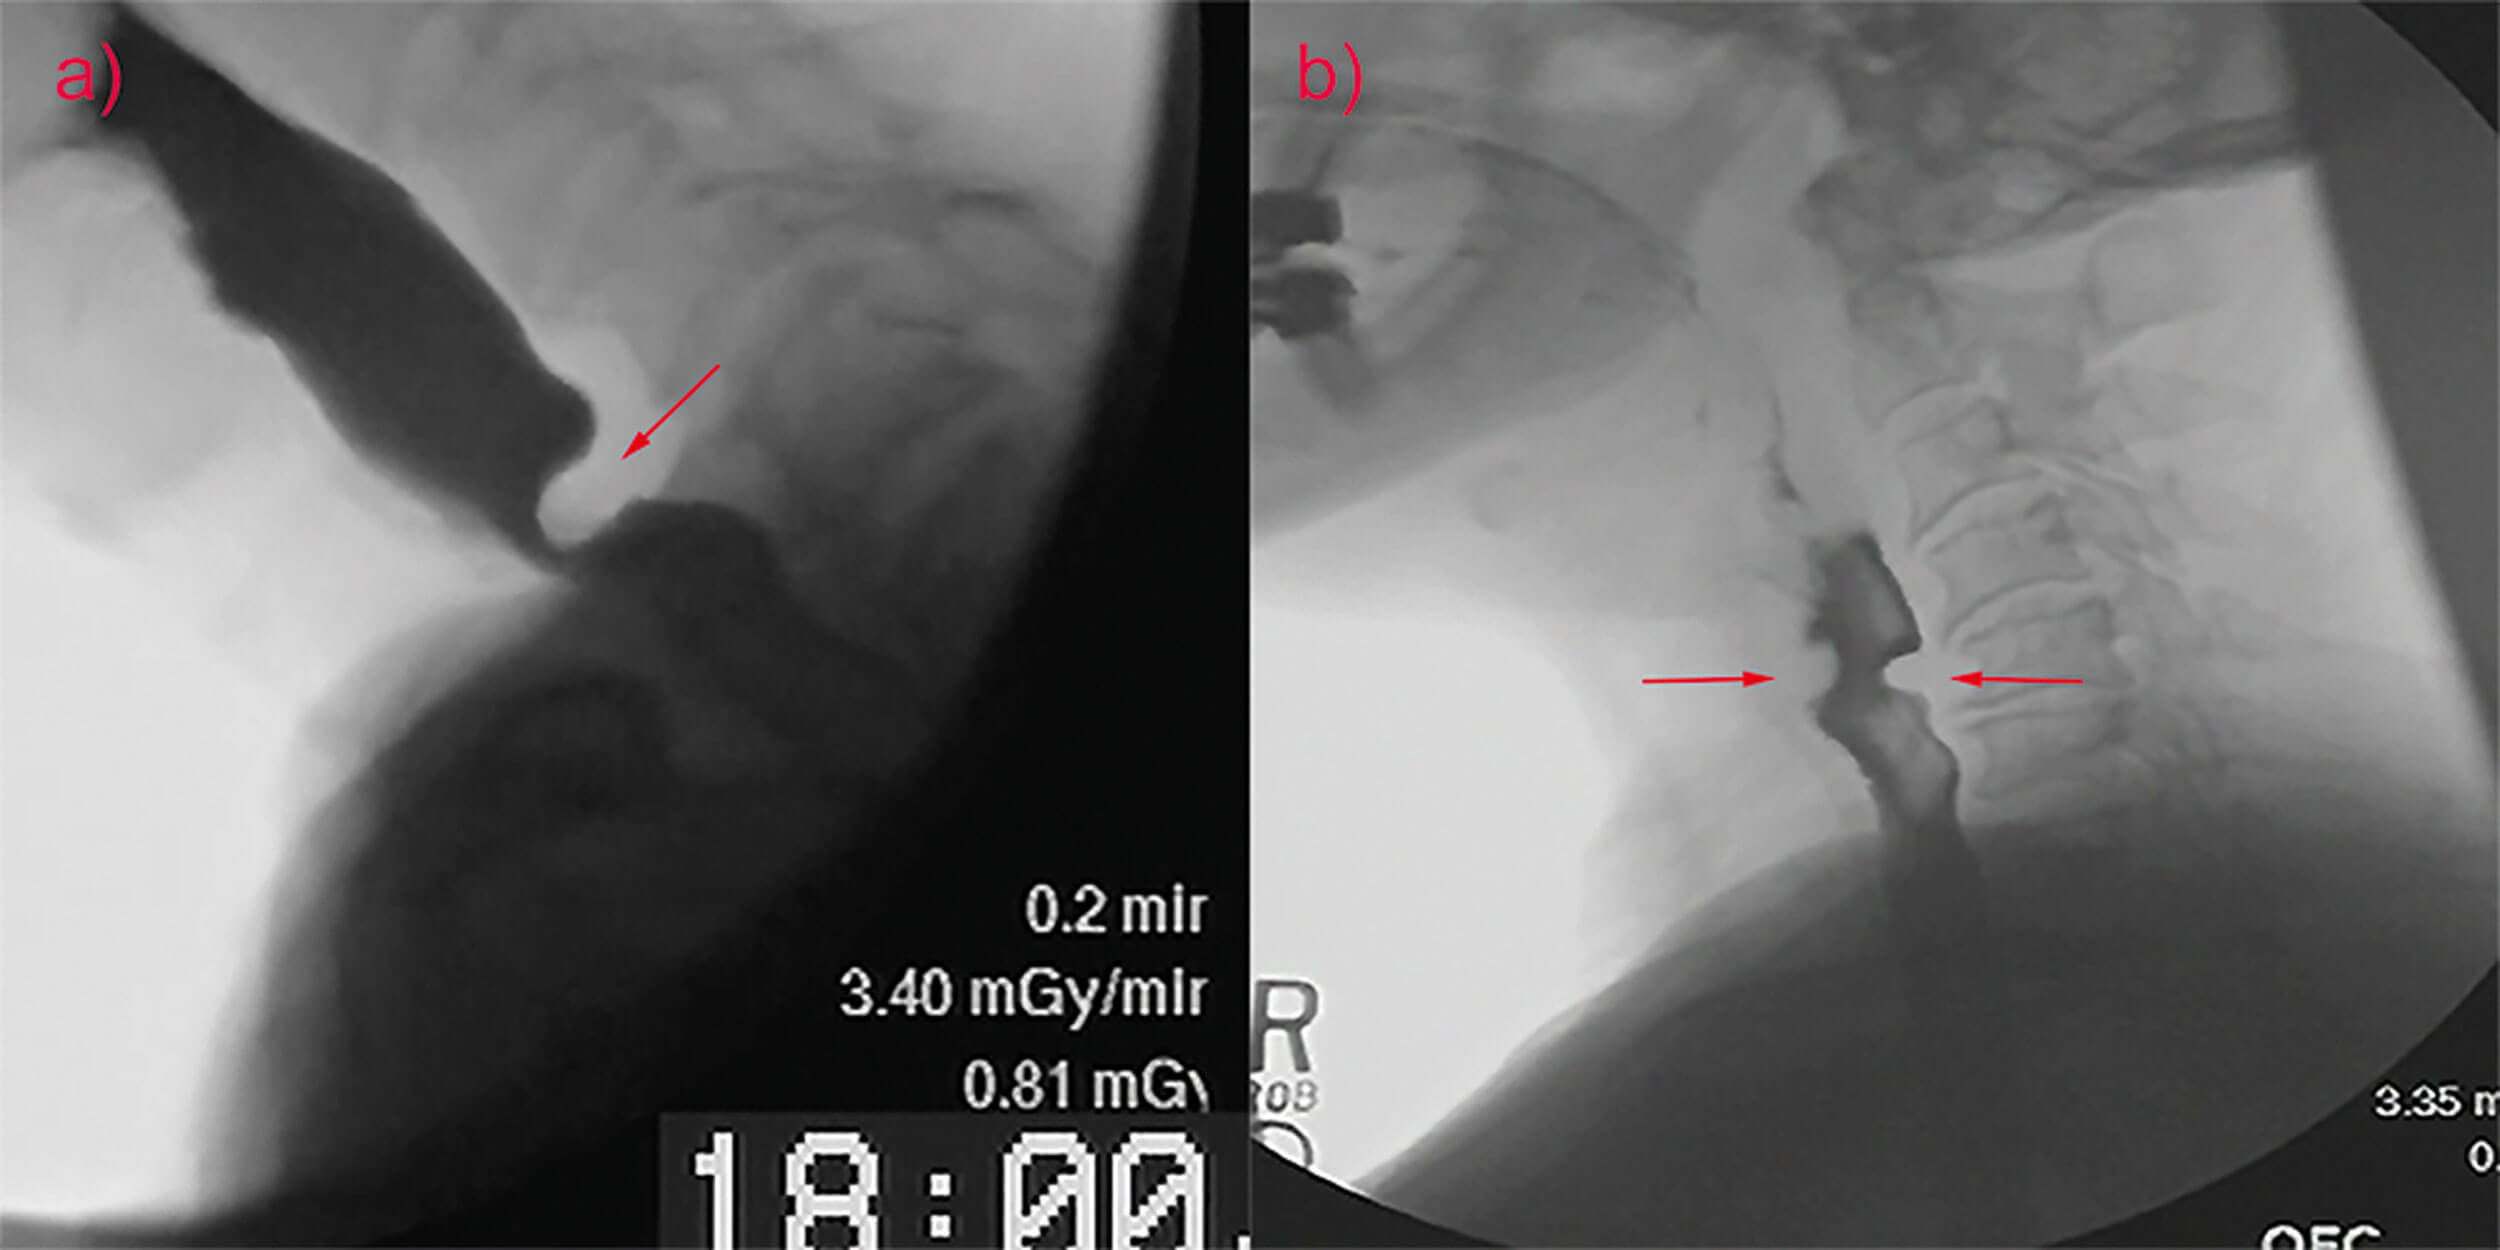

Muscle tension dysphagia: an underdiagnosed problem

In this article, the authors introduce the description of swallowing problems which have been recently attributed to muscle tension dysphagia (MTDg). The authors are clear that this is a diagnosis of exclusion, and it is important to rule out other...